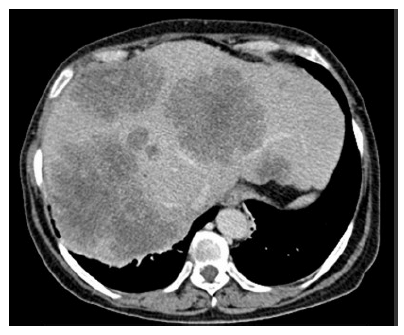

Paciente do sexo feminino, 62 anos de idade, relata dor abdominal em hipocôndrio direito há cerca de 1 mês e emagrecimento de 10 kg nos últimos 6 meses. Sem outras comorbidades. Nega história familiar de câncer de intestino. Ao exame físico: anictérica, palpada hepatomegalia dolorosa. A tomografia computadorizada de abdome evidenciou múltiplas metástases hepáticas inoperáveis e não passiveis de conversão. Tomografia computadorizada de tórax normal. CEA = 2.000 ng/ml. Colonoscopia mostrou lesão ulcerada em cólon sigmoide, ocupando 90% da luz do órgão. A biópsia da lesão em sigmoide confirmou adenocarcinoma de cólon. Pesquisa da mutação KRAS foi positiva.